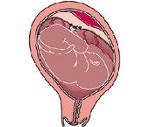

Плацентарная поверхность матери с огромной плацентарной гематомой в верхней части.